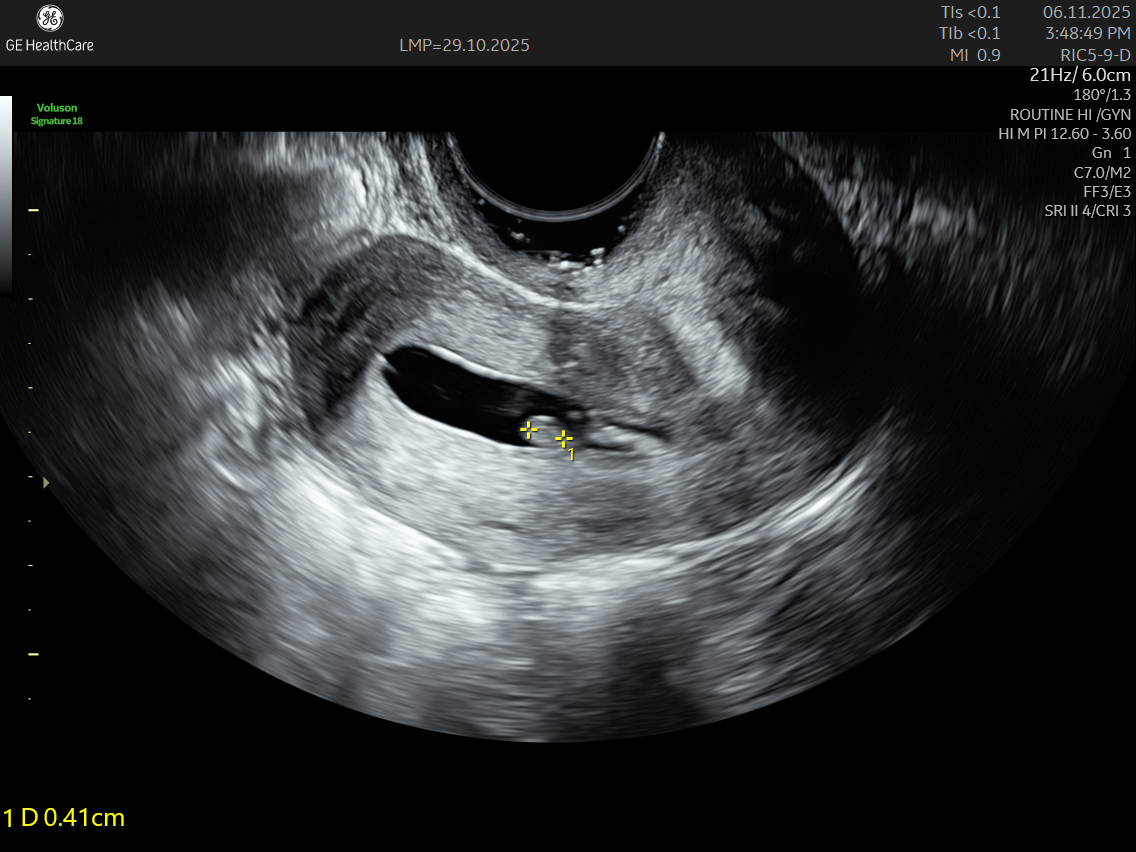

• A transvaginal ultrasound is performed simultaneously to capture detailed images.

IMAGE GALLERY